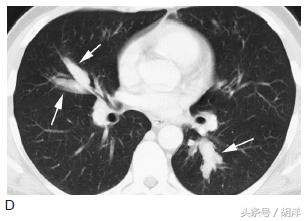

变态反应性支气管肺曲菌病

这种态势是身体本身为过敏体质,长期合并曲菌吸入,身体因为严重的过敏反应形成大量粘稠的粘液栓塞在气管中,很容易形成中央型支气管扩张,患者同时伴有哮喘样发作,很容易和哮喘混淆,但使用抗哮喘药物无效。

箭头所指为粘液栓和支气管扩张